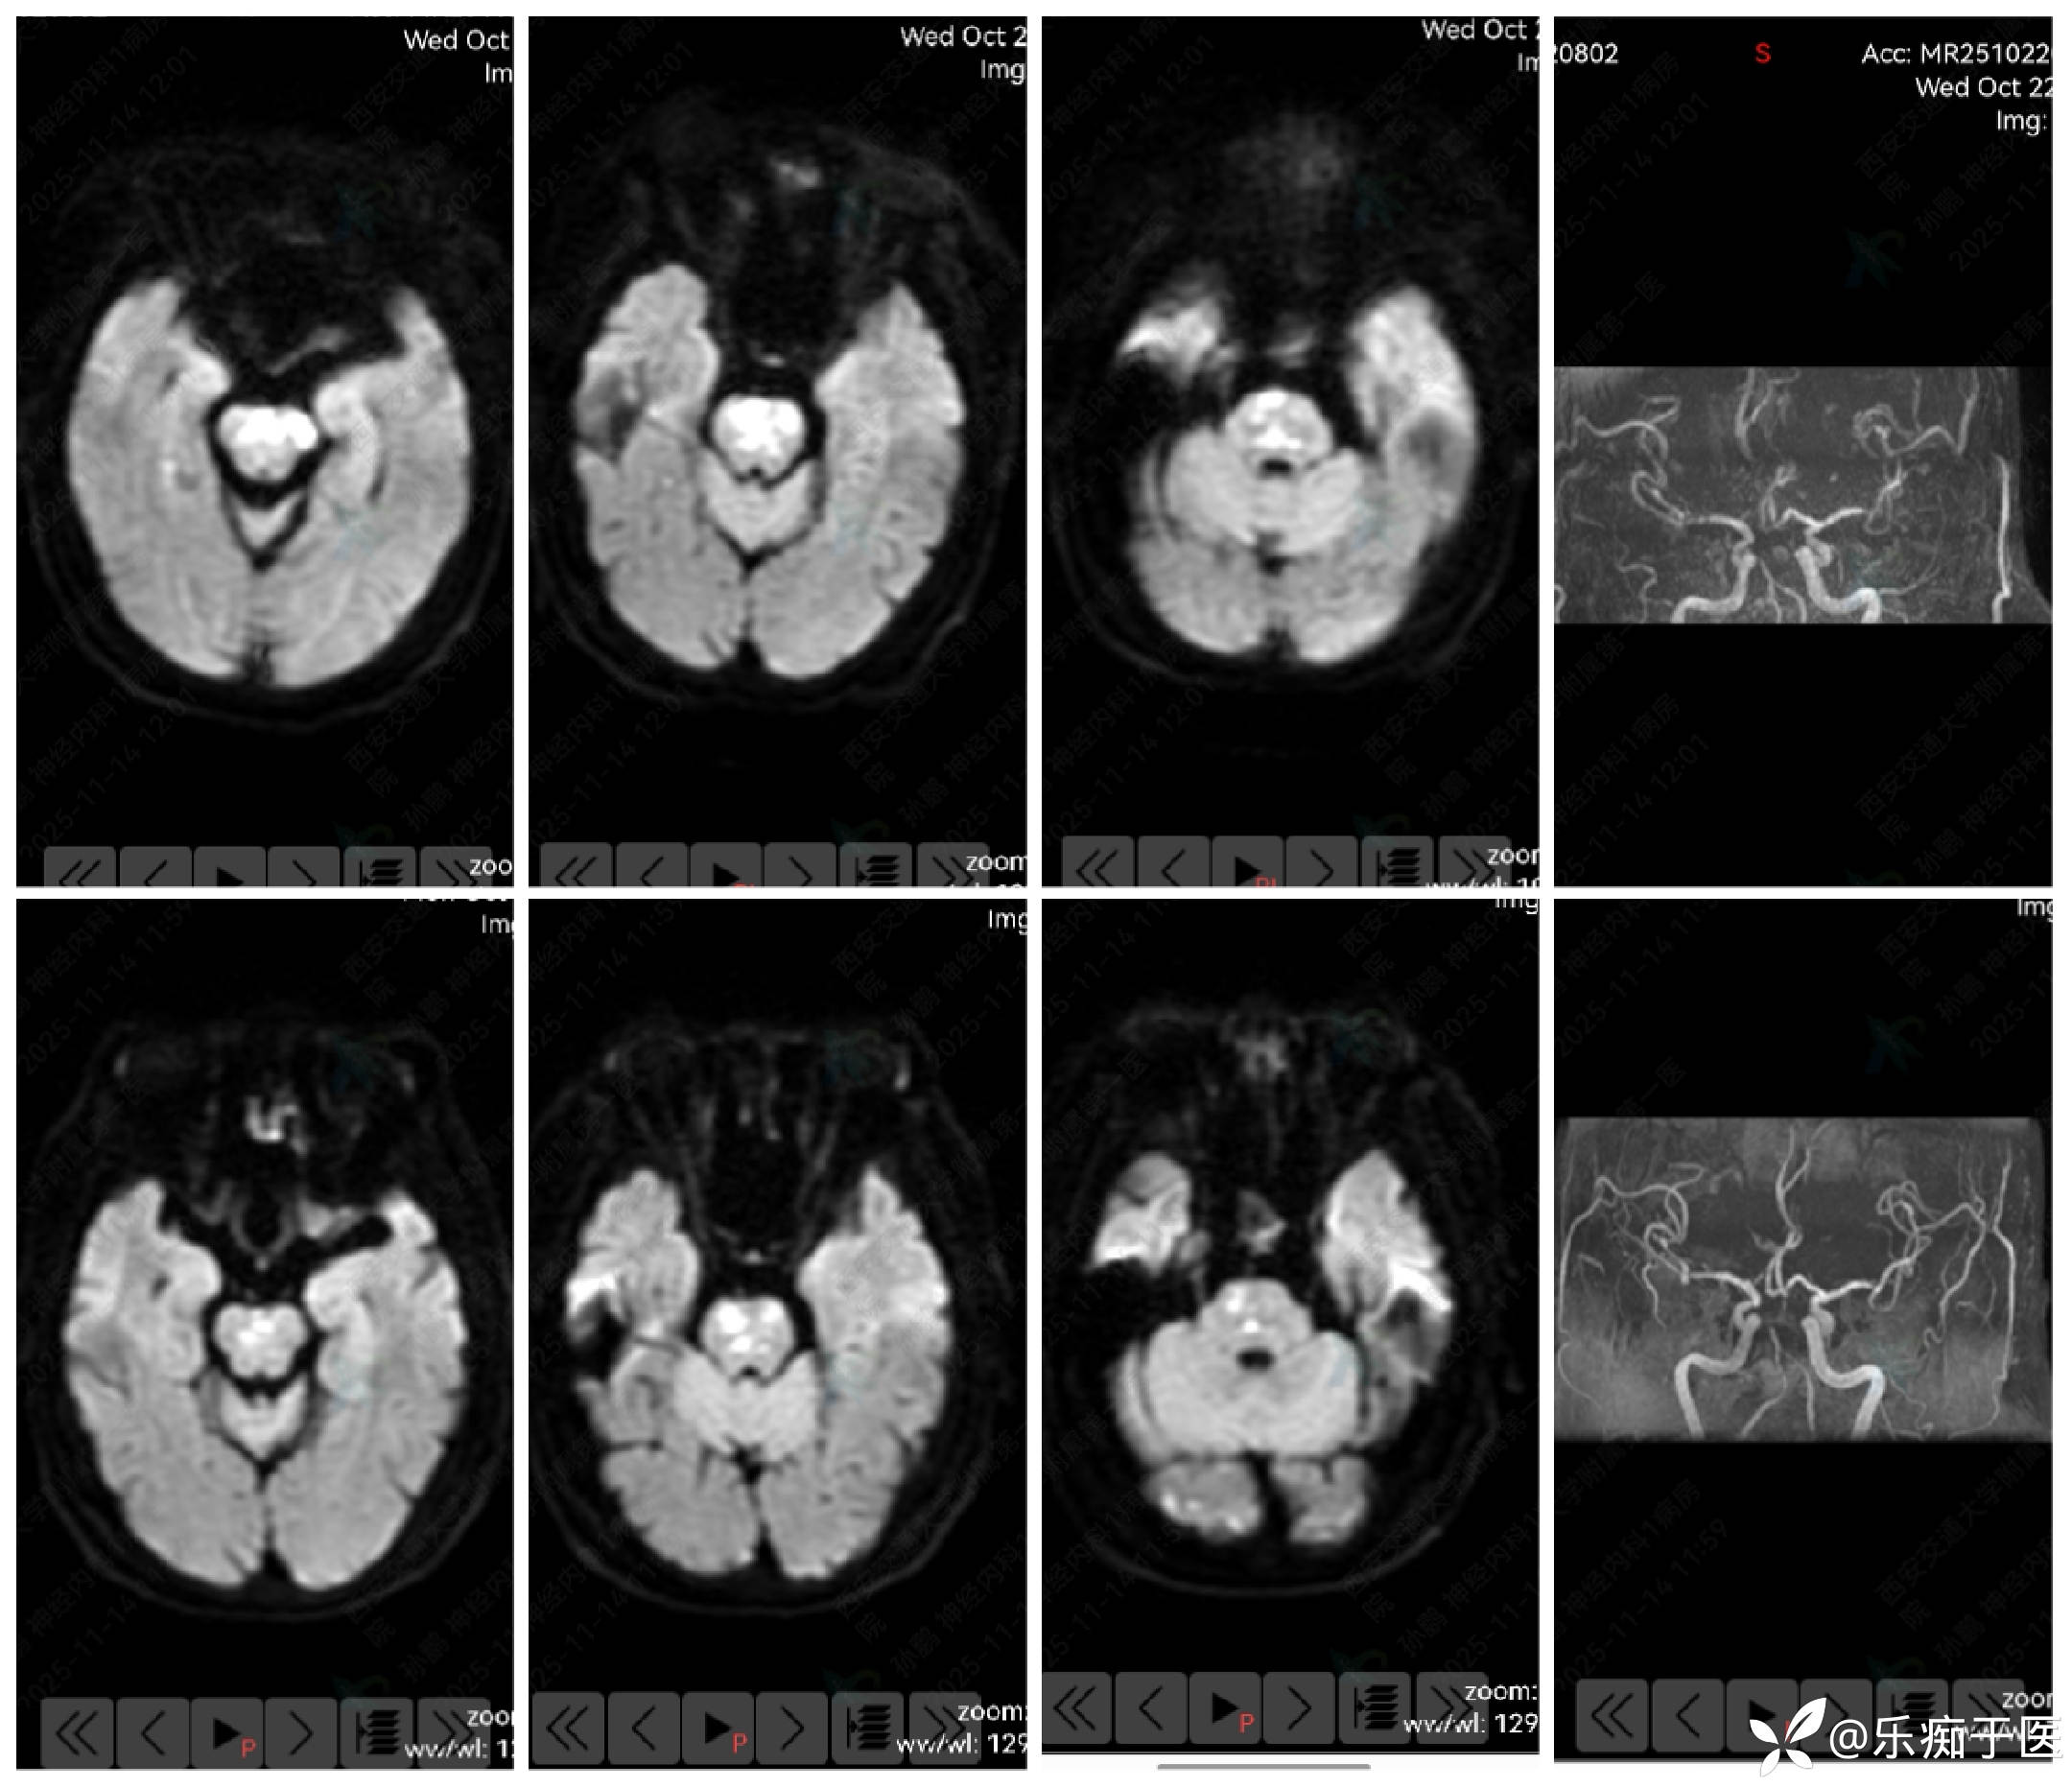

上:加重后 下:加重前

加重后:嗜睡,构音障碍明显加重,中枢性面瘫,右侧肢体2级,左侧肢体肌力3级,双侧病理征阳性。